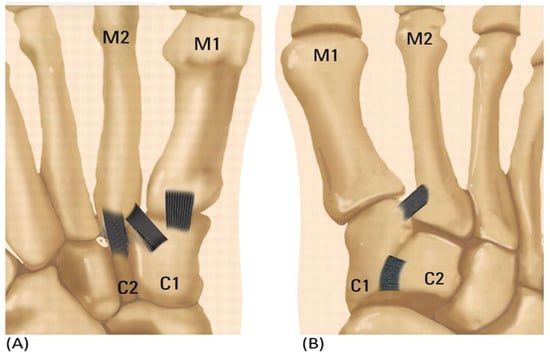

| C1–M2 | Medial cuneiform—second metatarsal bone damage with diastasis |

| C1–C2 | Medial cuneiform—intermediate cuneiform instability |

| C1–M1 | Medial cuneiform—first metatarsal bone instability |

| C2–M2 | Intermediate cuneiform—second metatarsal bone instability |